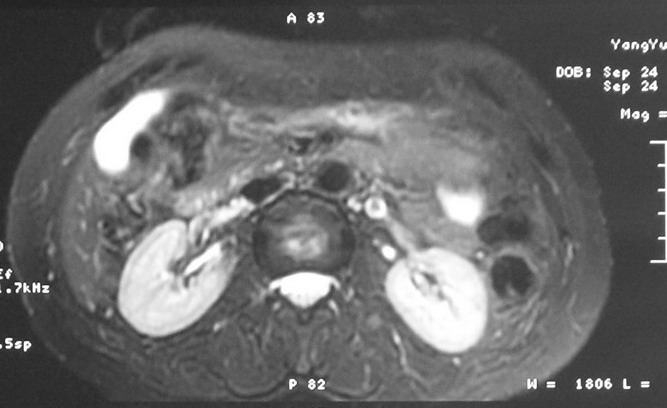

标题: MRI2066:腹膜后占位,请会诊,CT18531近期扫描图像

无明显不适,体检发现,

mri基本排除血管类肿瘤,明显强化说明极富血供,临床无症状,考虑胰岛细胞瘤可能大。

强化明显,并见有血管与之相连;考虑巨淋巴增生症.

极富血供的占位性病变,首先考虑良性,期待结果。